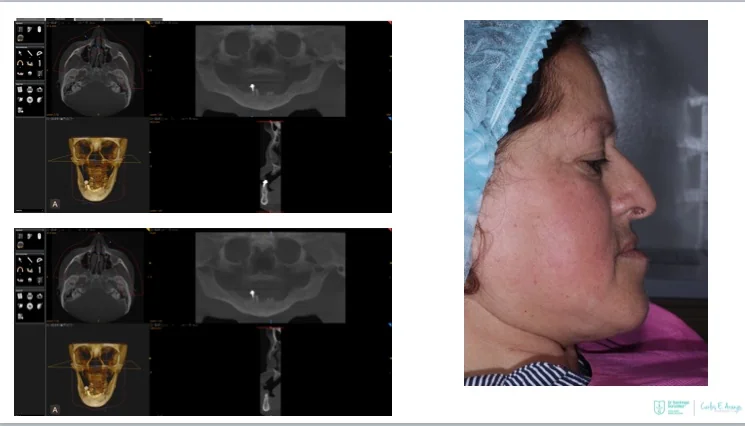

What is the All-on-4 treatment concept?

The All-on-4® treatment concept is a cost-efficient, graftless solution that provides patients with a fixed full-arch prosthesis on the day of surgery.

Characteristics include:

- Full-arch rehabilitation with only four implants

Two straight anterior implants and two implants tilted up to 45º in the posterior - Immediate Function (fixed provisional bridge)

For patients meeting criteria for immediate loading of implants - Graftless Procedure: Bone grafting is avoided by tilting the posterior implants, utilizing available bone.